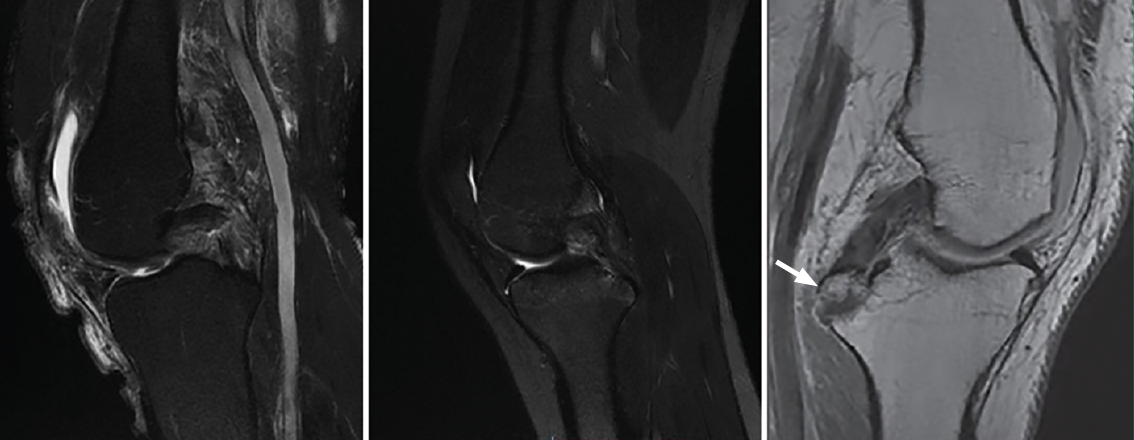

Although the diagnosis of PCL rupture is essentially clinical, and instability is quantified from stress radiographs, magnetic resonance imaging (MRI) is the technique of choice for the diagnosis and follow-up of PCL lesions subjected to conservative management, and affords excellent information on the presence of associated injuries - not only ligament damage but also meniscal or chondral lesions. In addition, MRI is able to distinguish between acute and chronic injuries, since the absence of soft tissue edema and of bone contusion (usually affecting the anterior portion of the tibia) is indicative of a chronic lesion(13,14).

Posterior cruciate ligament injuries are divided into three types according to their MRI characteristics: partial or intrasubstance lesions (Figure 6A), complete lesions (Figure 6B) and avulsion fractures at the tibial insertion (Figure 6C)(13,14). Most complete lesions occur in the middle portion of the ligament, which is not correctly visualized in the axial and coronal planes; the gold standard therefore is evaluation of images in the sagittal plane(13,14).

Figure 6. A: magnetic resonance imaging (MRI) sagittal view in T2-weighted sequencing, showing partial rupture; B: complete rupture of the posterior cruciate ligament (PCL); C: MRI sagittal view in T1-weighted sequencing of the left knee. The white arrow indicates avulsion of the PCL with a bone fragment in the tibial insertion.